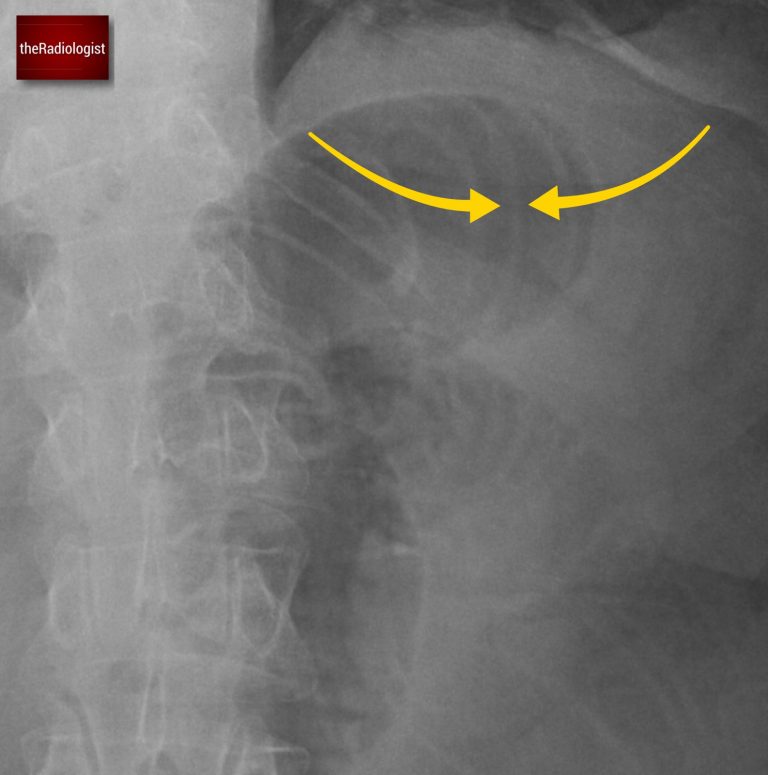

Look at the indentations on the bowel wall. With small bowel look out for valvulae conniventes (yellow arrow) that traverse the whole bowel wall: we can see this here, this is small bowel dilatation.